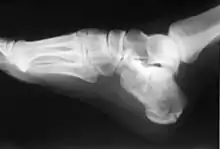

In humans and many other primates, the calcaneus (/kælˈkeɪniəs/; from the Latin calcaneus or calcaneum, meaning heel[1]) or heel bone is a bone of the tarsus of the foot which constitutes the heel. In some other animals, it is the point of the hock.

In humans, the calcaneus is the largest of the tarsal bones and the largest bone of the foot. Its long axis is pointed forwards and laterally.[2] The talus bone, calcaneus, and navicular bone are considered the proximal row of tarsal bones.[3] In the calcaneus, several important structures can be distinguished:[3]

The calcaneus is part of two joints: the proximal intertarsal joint and the talocalcaneal joint. The point of the calcaneus is covered by the calcanean bursa.